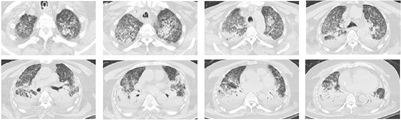

7月9日呼吸机氧浓度100%,PaO2,PaCO2,pH,并出现昏迷,血压下降,少尿。予上VV-ECMO后,并予镇静、镇痛和肌松。采用肺保护性通气策略,间歇正压通气(intermittent positive pressure ventilation,IPPV)模式,Vt 300 ml,呼气末正压通气(positive end-expiratory pressure, PEEP)10mmH2O,设置平台压25 cmH2O,f 16次/min。严格限制液体入量在2000 ml左右,使每日的出入量维持在适度的负平衡。7月14日在ECMO上机的情况下复查胸部CT,见双肺斑片状、条状影较前明显增多,且有弥漫性毛玻璃样渗出(图2)。7月13日~7月16日多次肺泡灌洗液均培养到耐碳青霉烯类鲍曼不动杆菌(carbapenem-resistant Acinetobacter baumannii,CRAB),7月15日将头孢哌酮钠舒巴坦钠更换为亚胺培南西司他丁钠(1g,静滴,每8 h给药1次),停用卡泊芬净,7月20日加用多粘菌素E超声雾化吸入。患者感染指标较前明显下降,ECMO氧浓度也逐渐下降,复查胸部CT显示双肺中下叶较前明显吸收,但双肺上叶渗出较前增加。